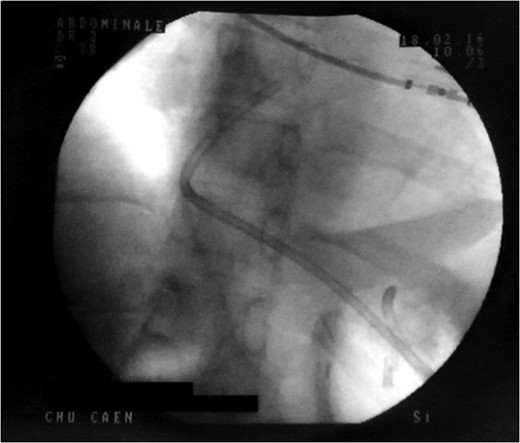

Control X-ray after the double pigtailed drain has been put up.

Proximal end of the double pigtail drain externalizes in the pericardium (arrow).